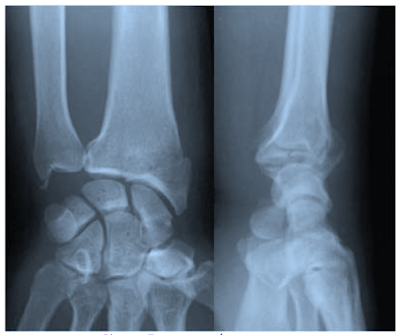

La plus fréquente et la plus grave, parce que rapidement arthrogène, des entorses intrinsèques du poignet est l'entorse Scapho - Lunaire: le poignet est tuméfié, la douleur est dorsale et latérale avec sensation d'instabilité et de ressaut lorsqu'on le mobilise: signe du "ballottement" et test de Watson (ce test est effectué en exerçant une pression sur la face palmaire du pôle distal du scaphoïde et en mettant la main en inclinaison radiale. Normalement le scaphoïde fléchit en inclinaison radiale. En faisant se test on bloque ce mouvement et on reproduit un ressaut douloureux car la flexion du scaphoïde se produit de façon brutale à la fin de la manoeuvre). Les radiographies de face mettent en évidence un écart scapho lunaire supérieur à 3 mm avec horizontalisation du scaphoïde; de profil le Semi Lunaire est basculé en arrière en DISI. L'arthrographie visualise la lésion ligamentaire.

L'autre forme clinique est l'entorse Luno - Pyramidale avec bascule vers l'avant en VISI du Semi- Lunaire sur les radiographies du poignet de profil. Conduite à tenir